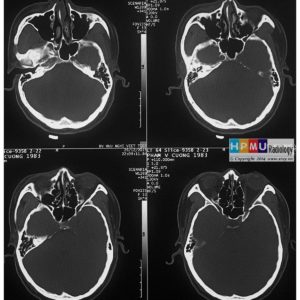

U dây VIII

Lượt xem: 140» 24-11-2018 -

U dây VIII

Lượt xem: 131» 24-11-2018 -

U dây VIII

Lượt xem: 143» 24-11-2018 -

U dây VIII

Lượt xem: 155» 24-11-2018 -

U dây VIII

Lượt xem: 124» 19-11-2018 -

U dây VIII

Lượt xem: 159» 05-11-2018 -

U dây VIII

Lượt xem: 239» 30-10-2018 -